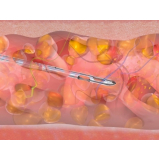

Abdominoplastia com Lipo

Há momentos em que é necessário ter por perto profissionais qualificados e dedicados à pronta recuperação do paciente. A FF Cirurgia Plástica oferece e coloca à sua disposição o que existe de mais atualizado em procedimento cirúrgico para abdominoplastia com lipo. Com o objetivo de levar qualidade à vida dos clientes, a instituição oferece infraestrutura adequada às necessidades de cada um: cuidado médico humanizado, realizado através de dedicação, profissionalismo e amor.